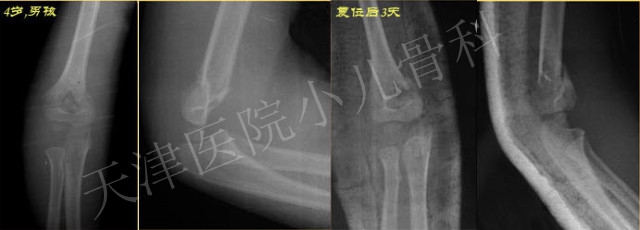

学生:4岁男孩,摔伤致“右肱骨髁上骨折”,急诊行骨折手法整复,您看复位后位置可以接受吗?

老师:从原始X线片看,正位示轻度尺偏,侧位示肱骨前缘线没有经过肱骨小头,骨折远端轻度向后移位,后方骨皮质部分相连,是典型的Gartland II型骨折。复位后片正位尺偏移位获得纠正,侧位平不标准不能很好判断“前倾角”恢复情况。